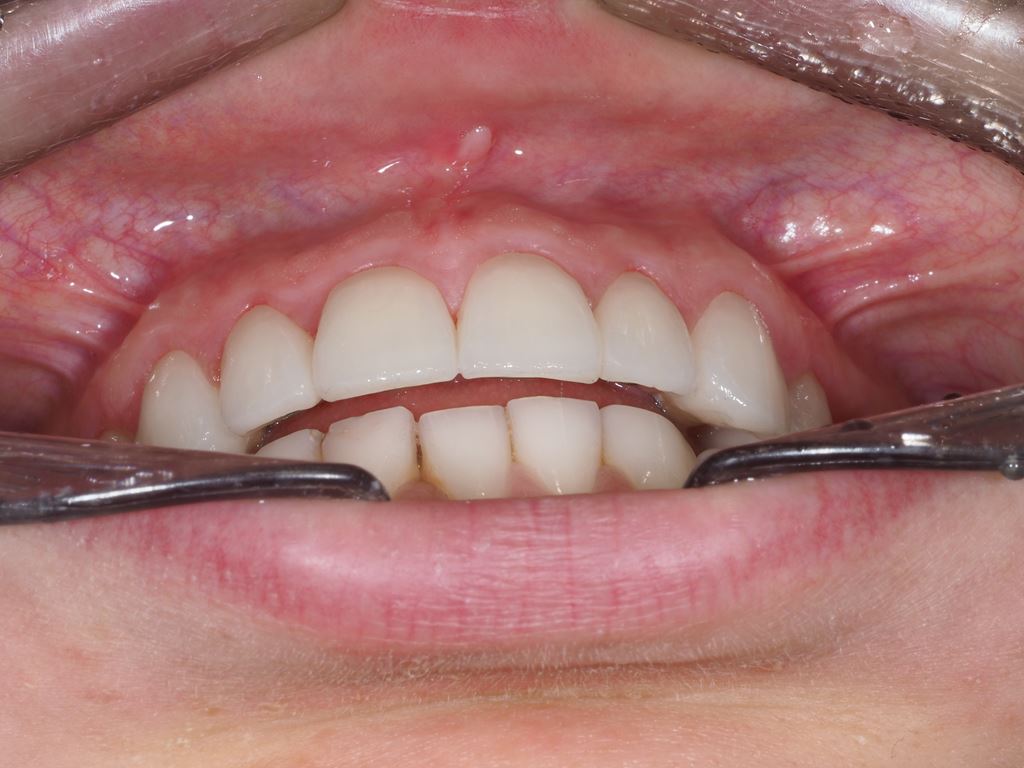

W pierwszym etapie diagnostycznym wykonano zdjęcia zewnątrz- i wewnątrzustne (ryc. 1-12).

Ryciny 39-50 przedstawiają stan po zakończeniu leczenia.